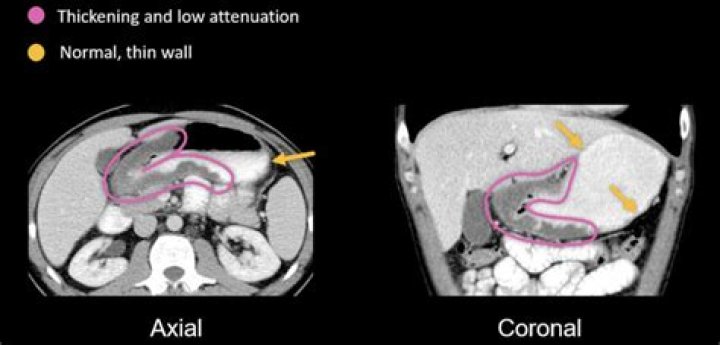

CT. Femoral hernias typically have a characteristic funnel-shaped neck. On axial CT images, the neck of the femoral hernia sac may be seen as a narrow protrusion through the femoral ring just medial to the common femoral vein. This can often look indented and compressed by the hernia sac.

TMT: CT Hernia Imaging (II): Femoral vs Inguinal, by Dr Jeshil Shah